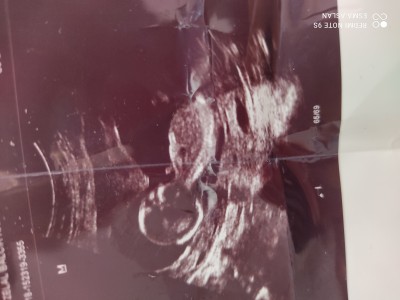

Tahmin yurutelimmi

Sorum yukarda16

Gebelik haftası

Burda bir bebek var

Benim bebeğim gibi yatıyor ve ultrason fotosu aynı gibi erkek demislerdi

Ya banada doktor 2 defa erkek dedi tahmin yürüttü sadece

Kiz gibi geldi bana da

Erkek gibi geldi bana.

Kız bence öğrenince yaz merak ettim

Eger kafası yuvarlaksa kız kafasının arkasi daha küt geliyosa erkek diye bi teori vardı :) ne kadar doğru bilemem tabi :) ben kıza benzettim

Erkek gibi ogrenince bizede haber ver

Erkeğe benziyor canım sağlıklı sıhhatli olsun inşallah Hayırlı olsun